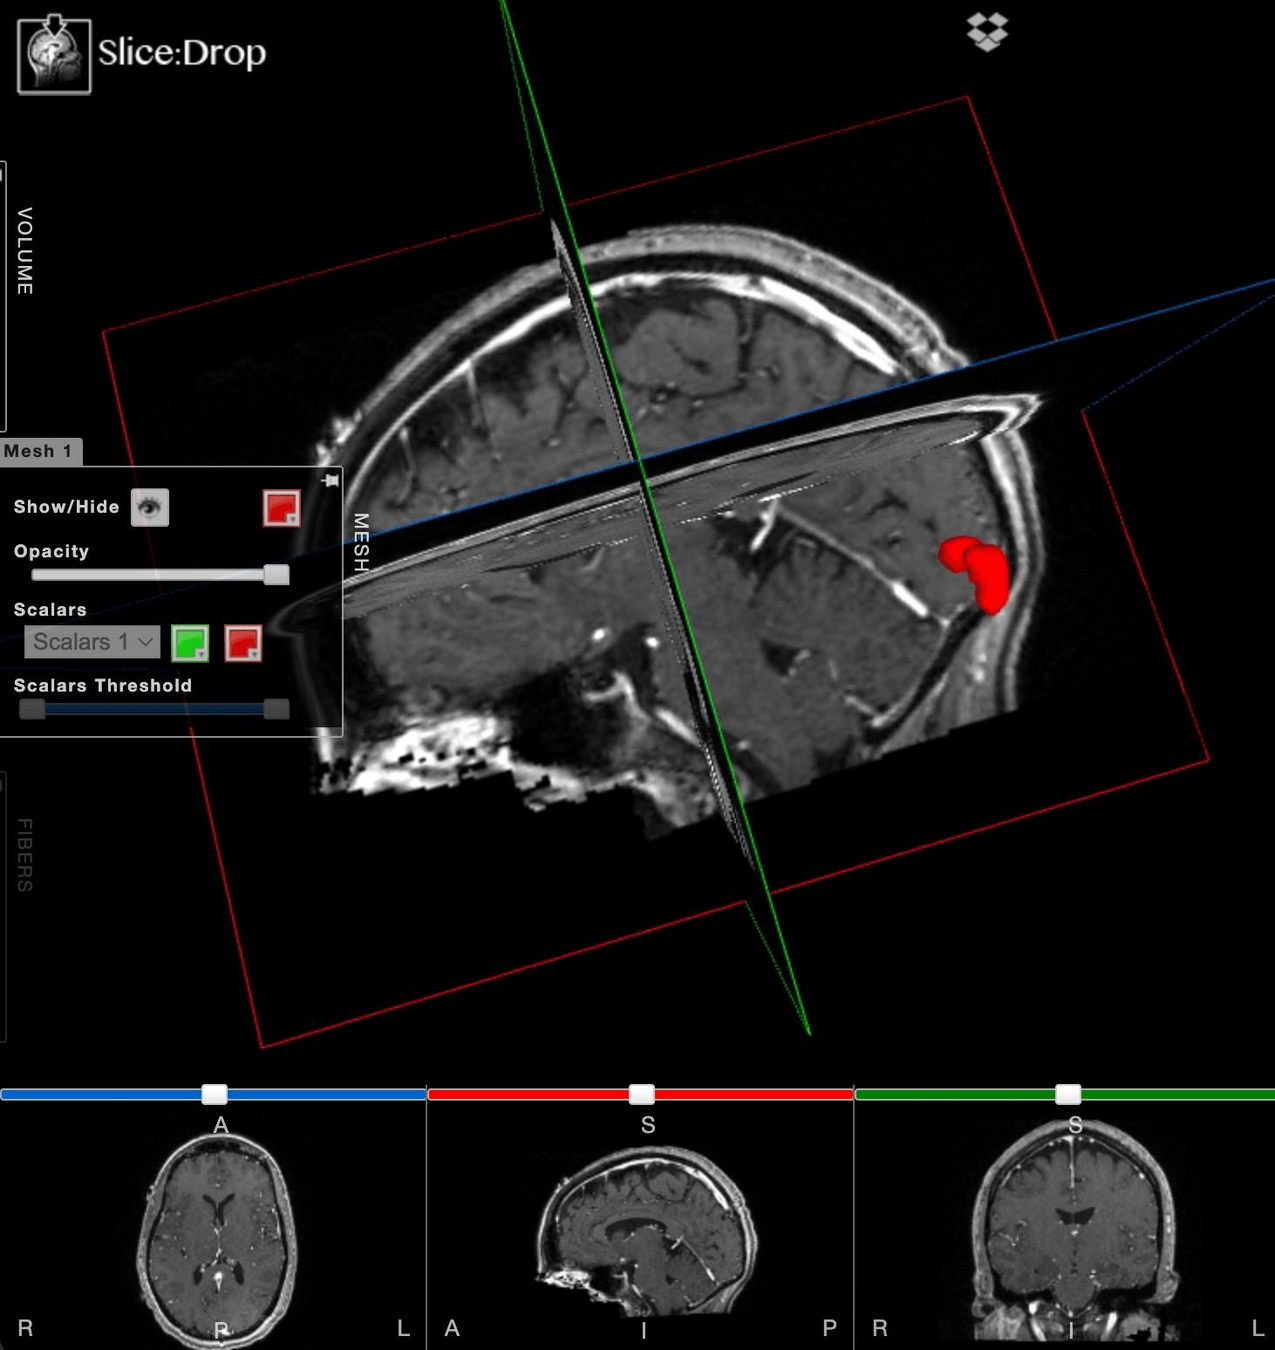

After export, let's load it in SliceDrop!

or BYOD!